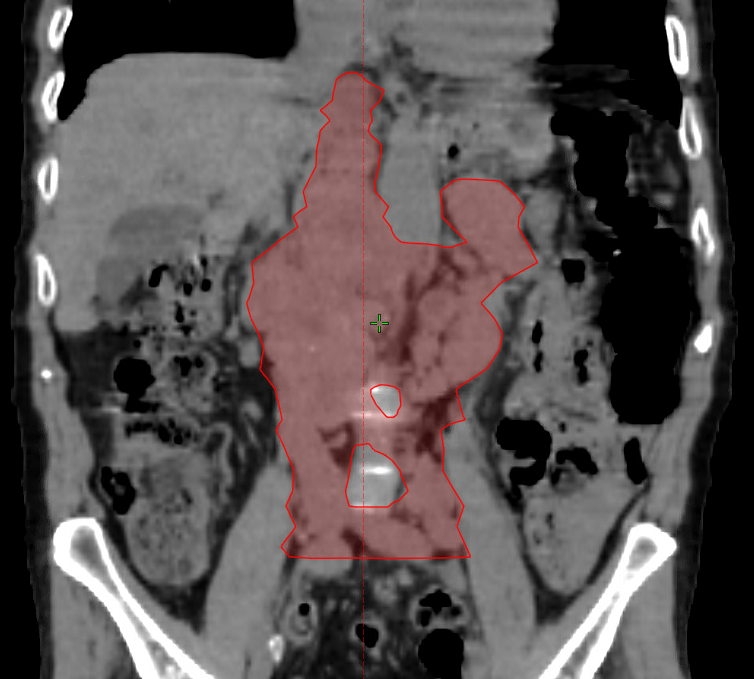

It's vessel. There's upstream venous congestion. Adenopathy is 7 cm AP/PA direction. There are some smaller nodes further south along the let iliac, but I had to stop somewhere. Resimming tomorrow after 12 Gy given shrinkage.Tough to tell what's adenopathy/bowel/vessel from one slice, but it looks like what I presume is a right common iliac node is getting short changed.